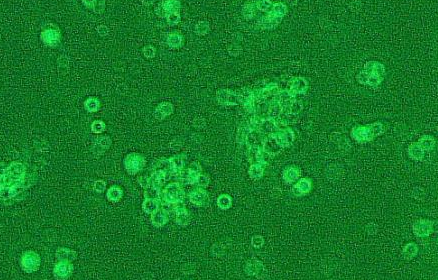

贴壁;上皮细胞样

形 态:贴壁;上皮细胞样

| HZ-H514 | HOP-92;人小细胞肺癌细胞 | 1×10^6 cells/瓶 | 询价 | 下载 |

4. 将培养瓶平放使胰酶浸没整个瓶壁的细胞层,计时约40s,立马竖起对着灯光可观察到细胞与HOP-92细胞之间有针孔样缝隙,并有1-2个细胞脱落,这时为胰酶消化的最适时机。若看到成片的细胞从瓶壁脱落为胰酶消化过度;若看不到针孔样缝隙和细胞脱落,则需继续消化,轻轻的迅速平放培养瓶使胰酶浸没细胞层1s后迅速竖起对着灯光观察细胞情况,可反复几次,直至出现针孔样缝隙和1-2个细胞脱落的最佳消化状态。用移液器将胰酶吸净。

5. 吸取1ml培养基于培养瓶内,并用移液器吸取少量的培养基轻柔的反复冲洗培养瓶壁5-8次,使贴壁HOP-92细胞完全脱落于培养基内再轻轻吹打2-3次,使细胞尽可能处于单个悬浮状态。

每天定时观察HOP-92细胞生长情况,一般72-96h后,细胞生长密度大于90%,即可进行细胞的传代或保株。